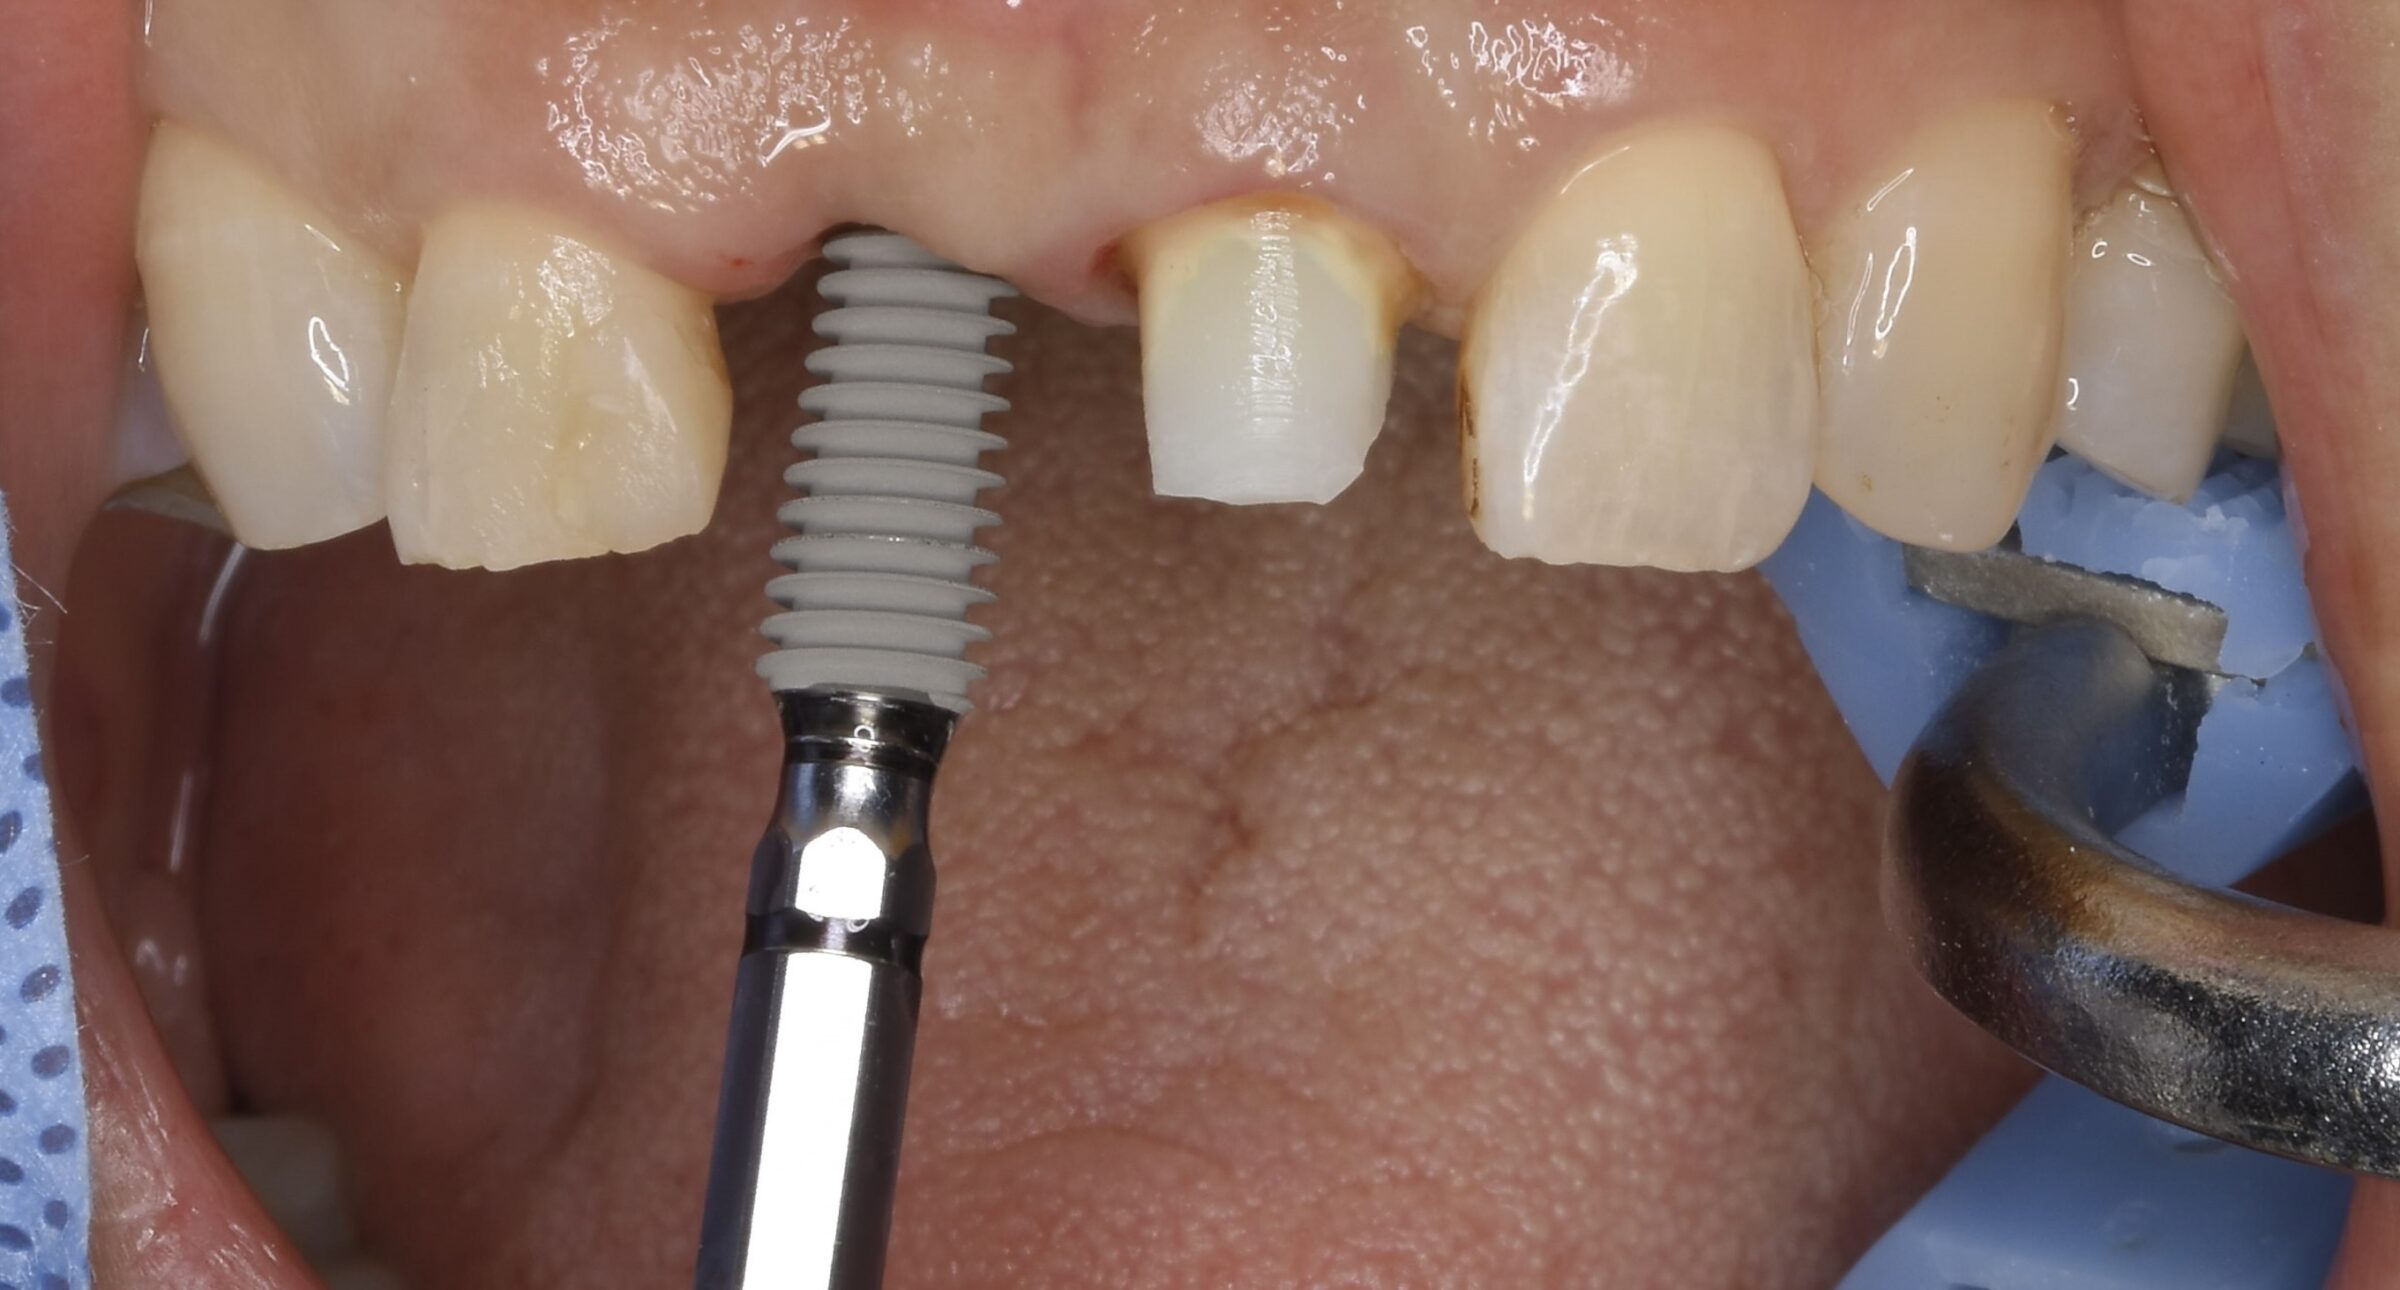

オペ中の口腔内写真とCT写真

失った前歯の箇所の歯茎の骨が痩せていることが分かります。

直径4ミリほどの穴を開けていきます。

このように逆回転でドリルを回していきます。

骨を削るのではく、骨を圧縮し広げることで、前歯のインプラントオペがシンプルかつスムーズに終わります。

ここまでのオペ時間はわずか10分。

出血もありません。

シミュレーションと同じ位置にインプラントが埋め込まれていることが分かります。